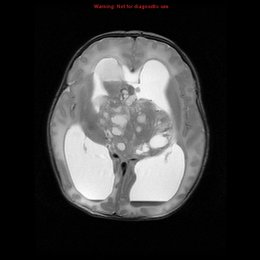

PREGUNTA 4 de 10

¿Cuál es el diagnóstico más probable de la siguiente imagen?

A)

βͺ

Quiste de la bolsa de Rathke

C)

Silla turca vacía

E)